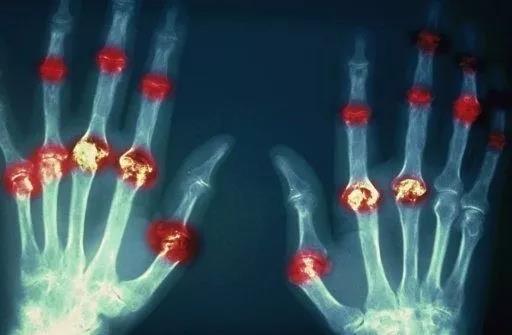

? 類風濕關節炎

類風濕關節炎是一種高度致殘的自身免疫性疾病,發病十年的患者中至少有50%的人失去勞動能力。

類風濕關節炎©Health Same of Flickr

1977年,Baldwin在用骨髓干細胞移植治療再生障礙性貧血的過程中,意外發現患者的類風濕關節炎得到緩解。

2004年,歐洲骨髓移植和抗風濕病聯盟對60例類風濕病關節炎移植患者進行回顧性分析,這些患者的關節破壞都達到不可修復程度,生活不能自理,通過干細胞移植治療后,67%的患者得到明顯緩解。

我國國內多家醫院已開展了干細胞治療類風濕性關節炎的臨床研究。首例自體干細胞移植治療類風濕關節炎在北京協和醫院完成。經過5個月隨訪,這些經常規藥物治療失敗且病情發展迅速的患者,在接受干細胞移植治療后,癥狀均獲得改善,關節腫脹消失,各項檢查指標恢復正常。

解放軍323醫院2011年的一項臨床研究中,27位患者(對照組)只使用藥物治療;另外153位患者(細胞治療組)在藥物治療的基礎上進行臍帶間充質干細胞輸注。結果顯示,治療組DAS28、HAQ 評分、ACR20較對照組下降明顯(分值越低,療效越好),Th1/Th2趨于平衡、Treg升高與臨床實驗指標及癥狀的緩解直接相關。